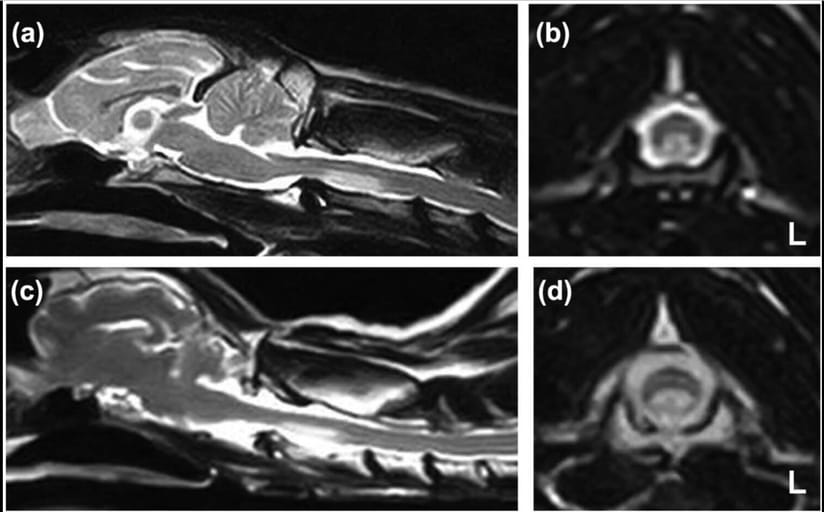

T2-weighted sagittal and transverse images of the cervical spinal cord of cats 1 (a,b) and 2 (c,d). A ventral hyperintense lesion is seen at the level of C2 on the sagittal images (a,c). An analogous ventral hyperintense elliptical lesion is seen in the transverse images (b,d) corresponding to the territory of the ventral spinal artery at C2